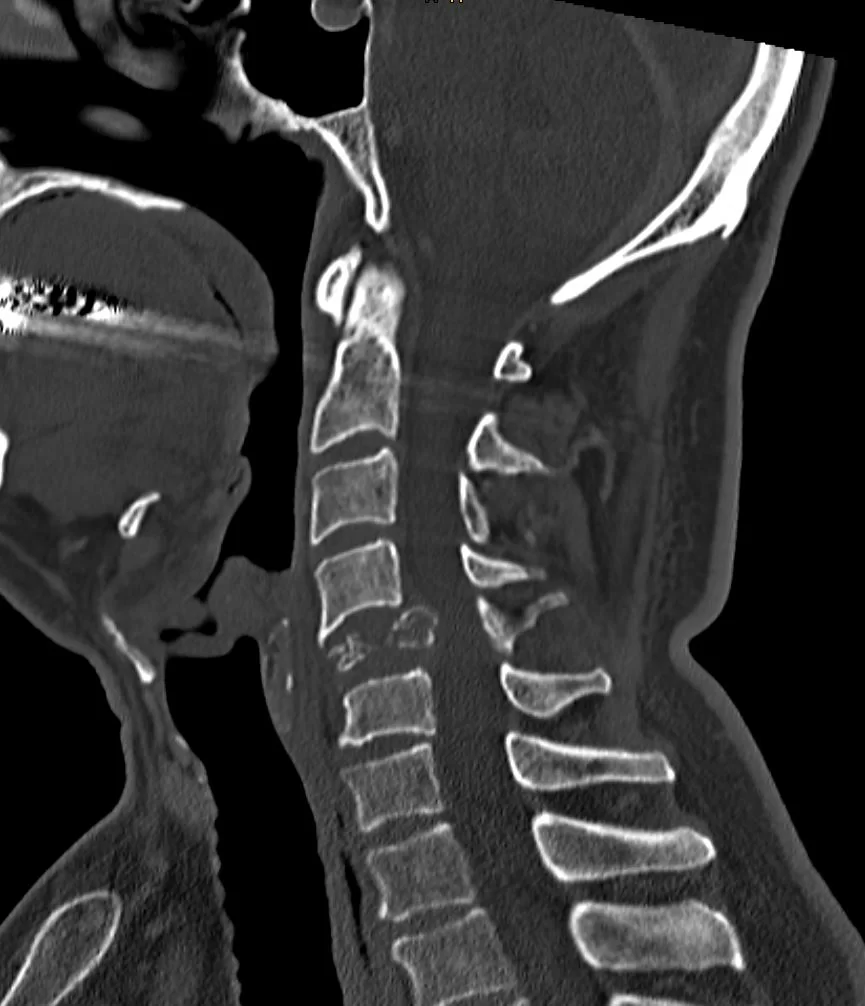

Παραγαγγλίωμα Α5 Σπονδύλου – Σωματεκτομή

Ασθενής άδρας 60 ετών με εμμένουσα αυχεναλγία (3 εβδομάδες) και πάρεση του δεξιού άνω άκρου απο πενθημέρου. Ο απεικονιστικός έλεγχος έλεγχος με μαγνητική και αξονική